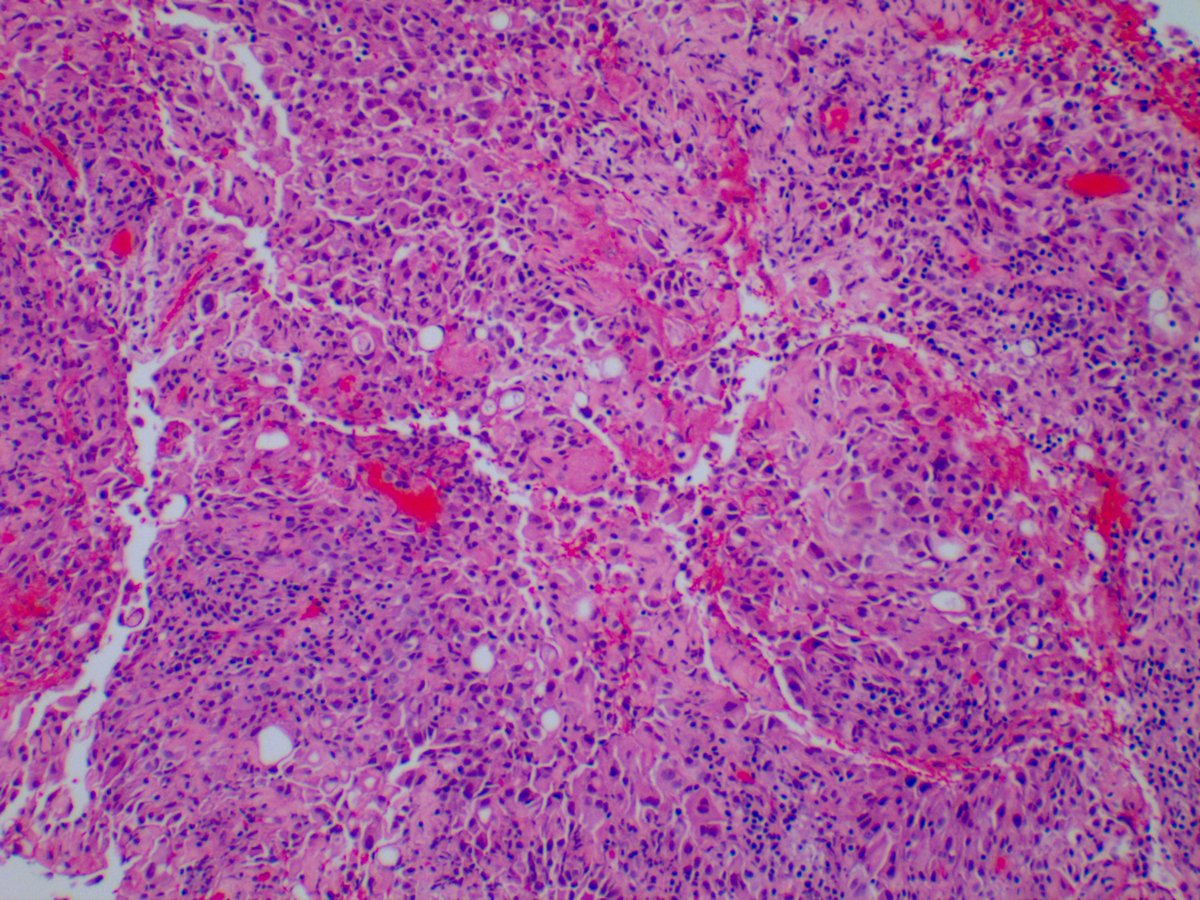

3. And I know this doesn't quite fit the 'pleural lesions' theme, but how about this 64-year-old male presenting with a pulmonary embolus after a heart transplant.

This lesion was first described by the late, great Rosai in 1997 who called this particular lesion a "histiocytoid hemangioma." Since that time, Cedars very own Dr. Luthringer published 14 cases and suggested which other cell type is present?

As the name suggests: mesothelial/monocytic incidental cardiac excrescences (cardiac MICE) is a rare lesion composed of reactive mesothelial cells and histocytes all bundled neatly together. Most cases are identified incidentally and have a benign course.